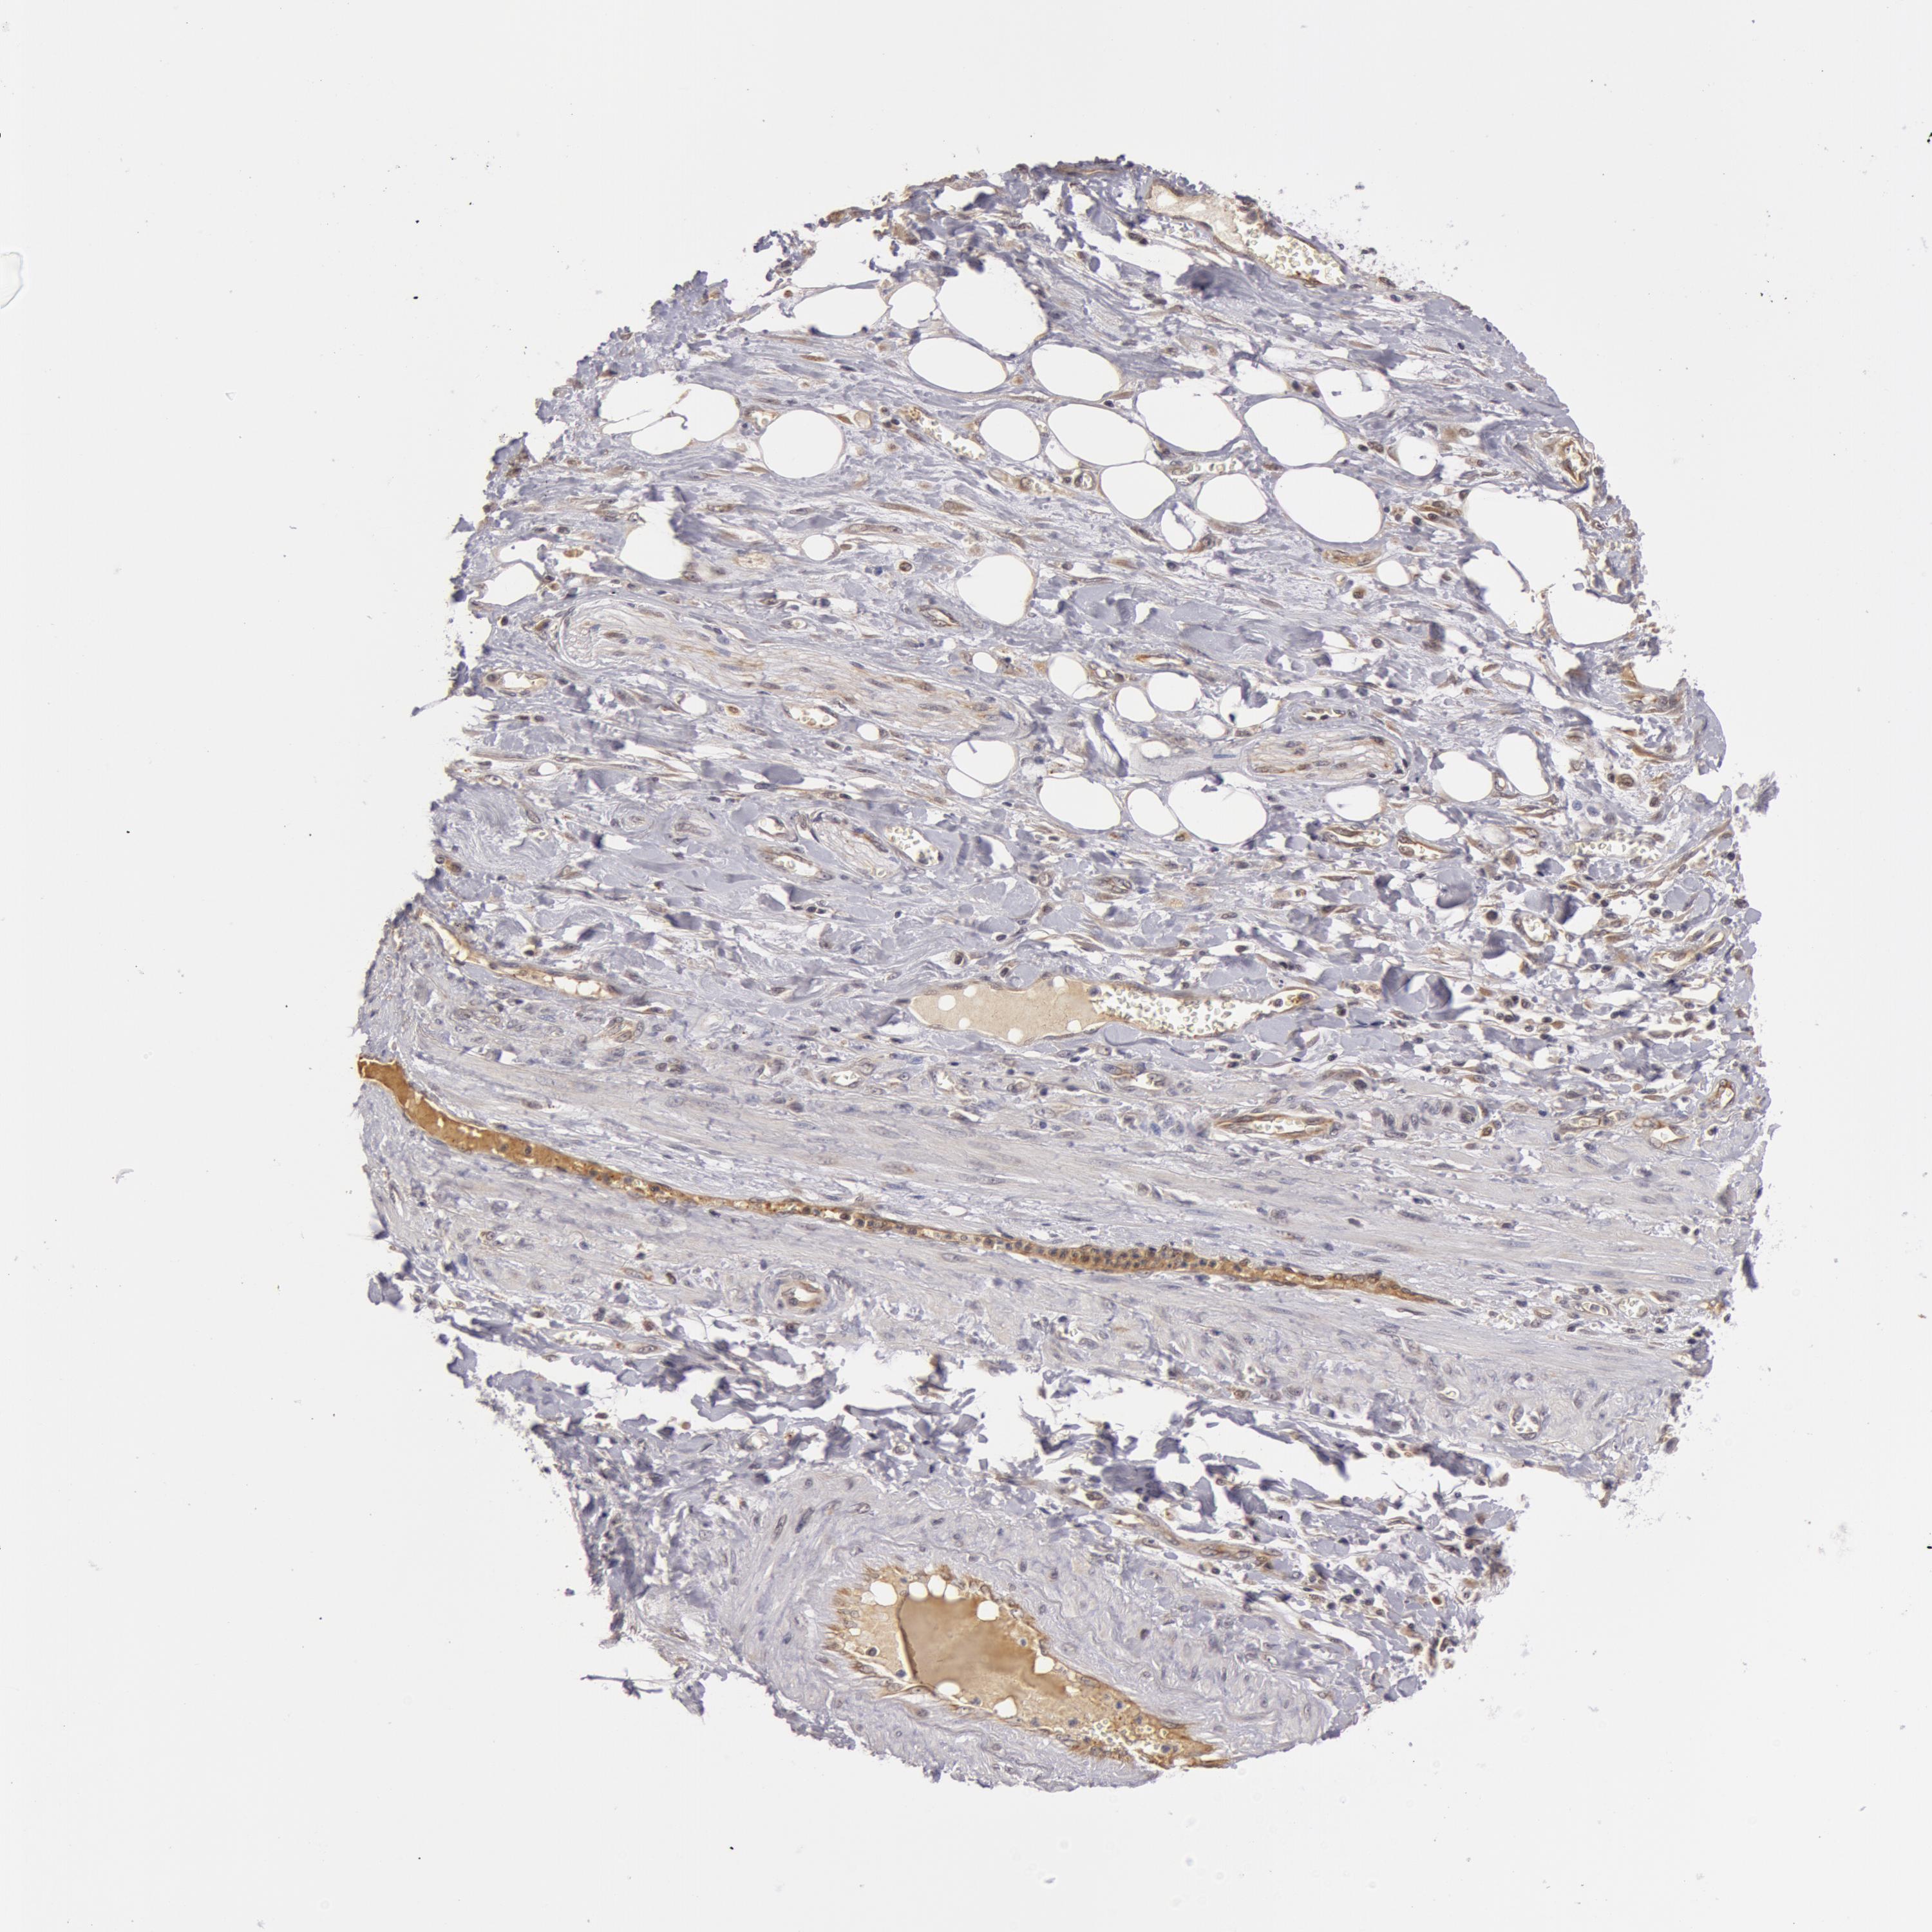

PANCREATIC CANCER - Protein expressioni

A mouse-over function shows sample information and annotation data. Click on an image to view it in a full screen mode. Samples can be filtered based on level of antibody staining by selecting one or several of the following categories: high, medium, low and not detected. The assay and annotation is described here.

Note that samples used for immunohistochemistry by the Human Protein Atlas do not correspond to samples in the TCGA dataset.

Antibody stainingi

Antibody staining in the annotated cell types in the current human tissue is reported as not detected, low, medium, or high, based on conventional immunohistochemistry profiling in selected tissues. This score is based on the combination of the staining intensity and fraction of stained cells.

Each image is clickable and will lead to virtual microscopy that enables deeper exploration of all samples and also displays staining intensity scores, fraction scores and subcellular localization as well as patient and tissue information for each sample.

Antibody HPA001475

Antibody HPA001589

Staining

High

Medium

Low

Not detected

Intensity

Strong

Moderate

Weak

Negative

Quantity

>75%

75%-25%

<25%

None

Location

Nuclear

Cytoplasmic/membranous

Cytoplasmic/membranous,nuclear

Adenocarcinoma, NOS